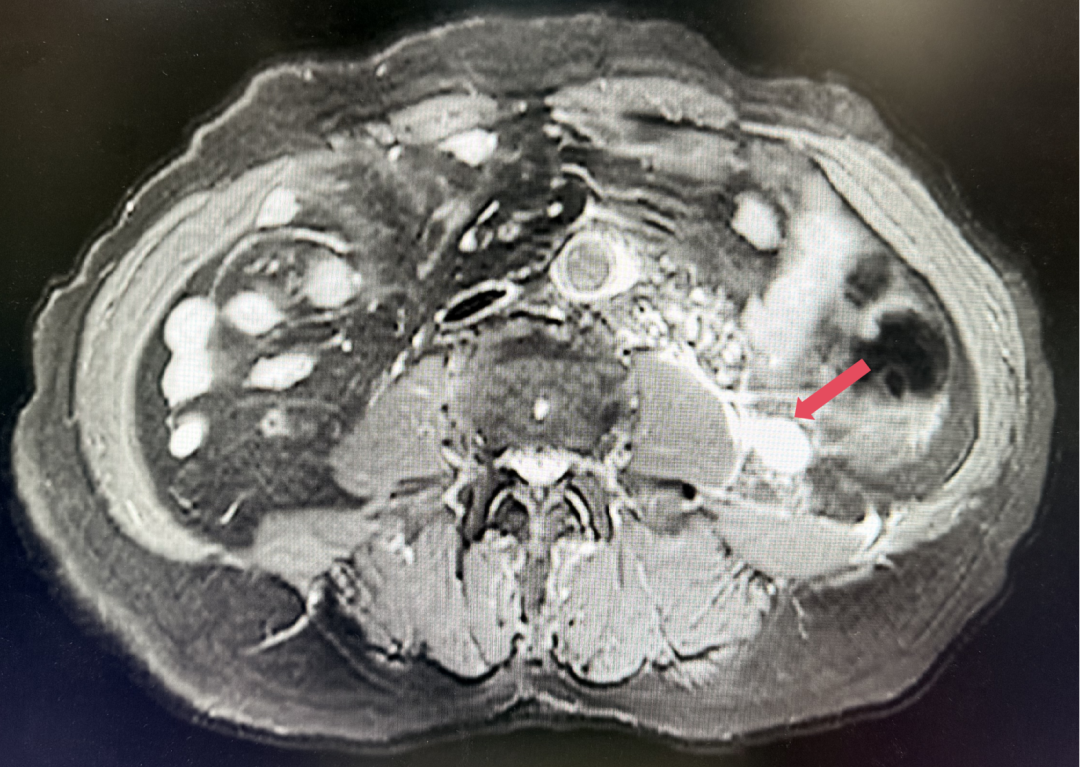

2023年3月:用药6周(C2)后首次肿评,肿瘤负荷减少至76.8mm,达到PR。

2023年3月,初始应答